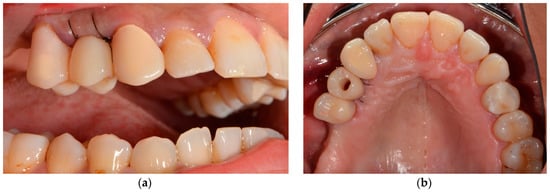

4. Surgical Procedures

5. Restorative Procedures

| Chairside, computer-aided design and milling of the provisionalization | |

| Placement of the chairside LTT |